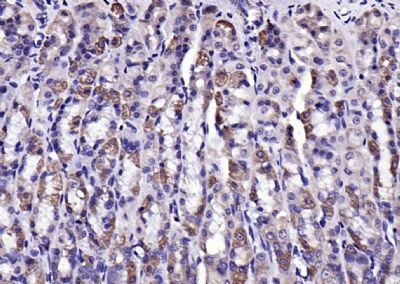

Paraformaldehyde-fixed, paraffin embedded (mouse stomach); Antigen retrieval by boiling in sodium citrate buffer (pH6.0) for 15min; Block endogenous peroxidase by 3% hydrogen peroxide for 20 minutes; Blocking buffer (normal goat serum) at 37°C for 30min; Antibody incubation with (LPA2) Polyclonal Antibody, Unconjugated (bs-2881R) at 1:200 overnight at 4°C, followed by operating according to SP Kit(Rabbit) (sp-0023) instructionsand DAB staining.